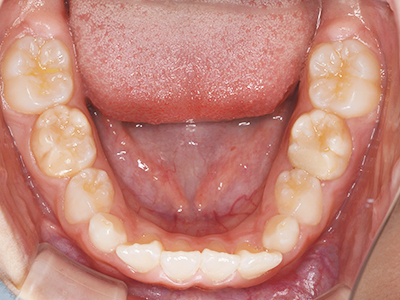

歯並びの相談に来られるお子様は、口呼吸をしているケースが多く、これが歯並びに大きな影響を与えています。

↓ - 下あごが狭くなる・下あごの位置が悪くなる

ないき歯科クリニックでは、上あごの成長不足を補い、鼻呼吸を獲得しつつ歯列を整え、将来のお口をより健康な状態にすることをゴールに定める矯正治療をおこなっています。